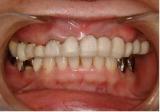

審美歯科治療 | ||

| 40代女性の患者さんです。再生療法などの様々な技術を用いて審美的に仕上げました。が最も大切なものは「咬み合わせ」です。見た目だけではいけません。(SHILLA SYSTEM使用) | ![]() |

【治療前】 |

【治療後】 |